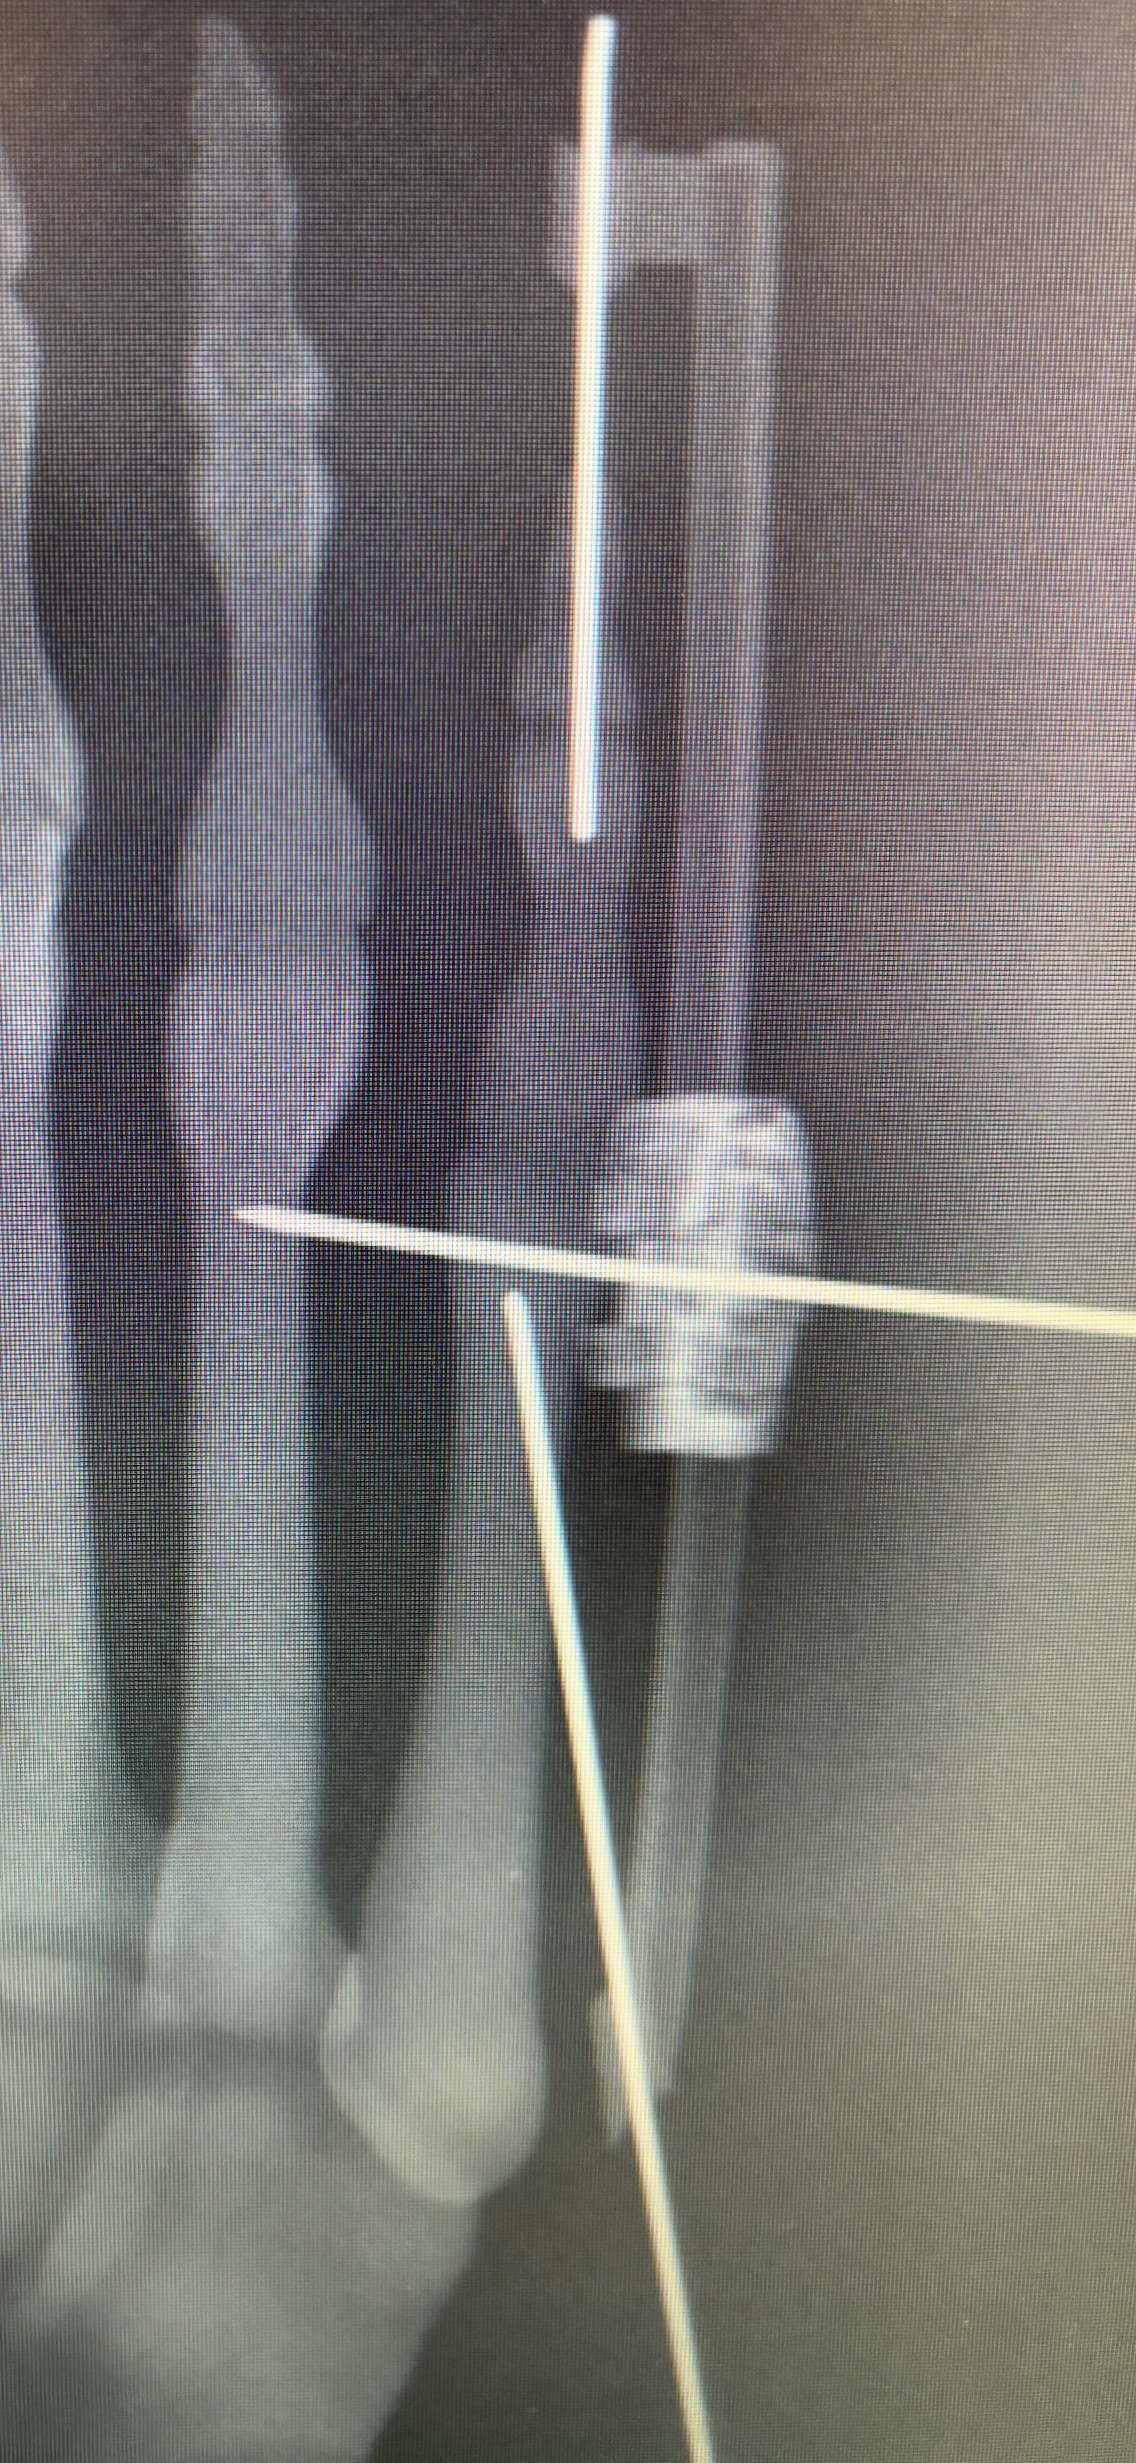

In 2024, we devised the Bunion-NET™ system to address the gaps in the minimally invasive portfolio for (Tailor’s) Bunionette correction. Our patented approach avoids the pitfalls of free-floating osteotomies and overcomes the limitations of stemmed implants with a seamless “2-stitch” approach